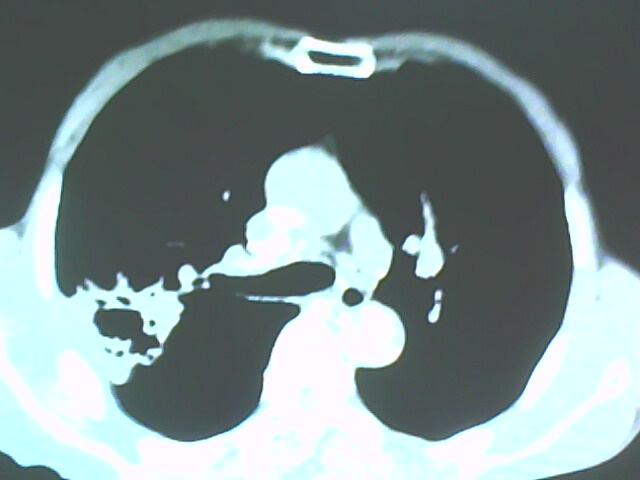

患者,男,66岁,以咳嗽、咳痰伴胸痛来就诊。

胸片提示右上肺占位病变。请各位老师看看ct。

从年龄及影像特征均支持癌性空洞。

右上肺后段肺癌:

典型癌性空洞(偏心性,壁厚薄不均,内壁不光整),周围毛刺较僵硬,且有刺突征和血管聚集征